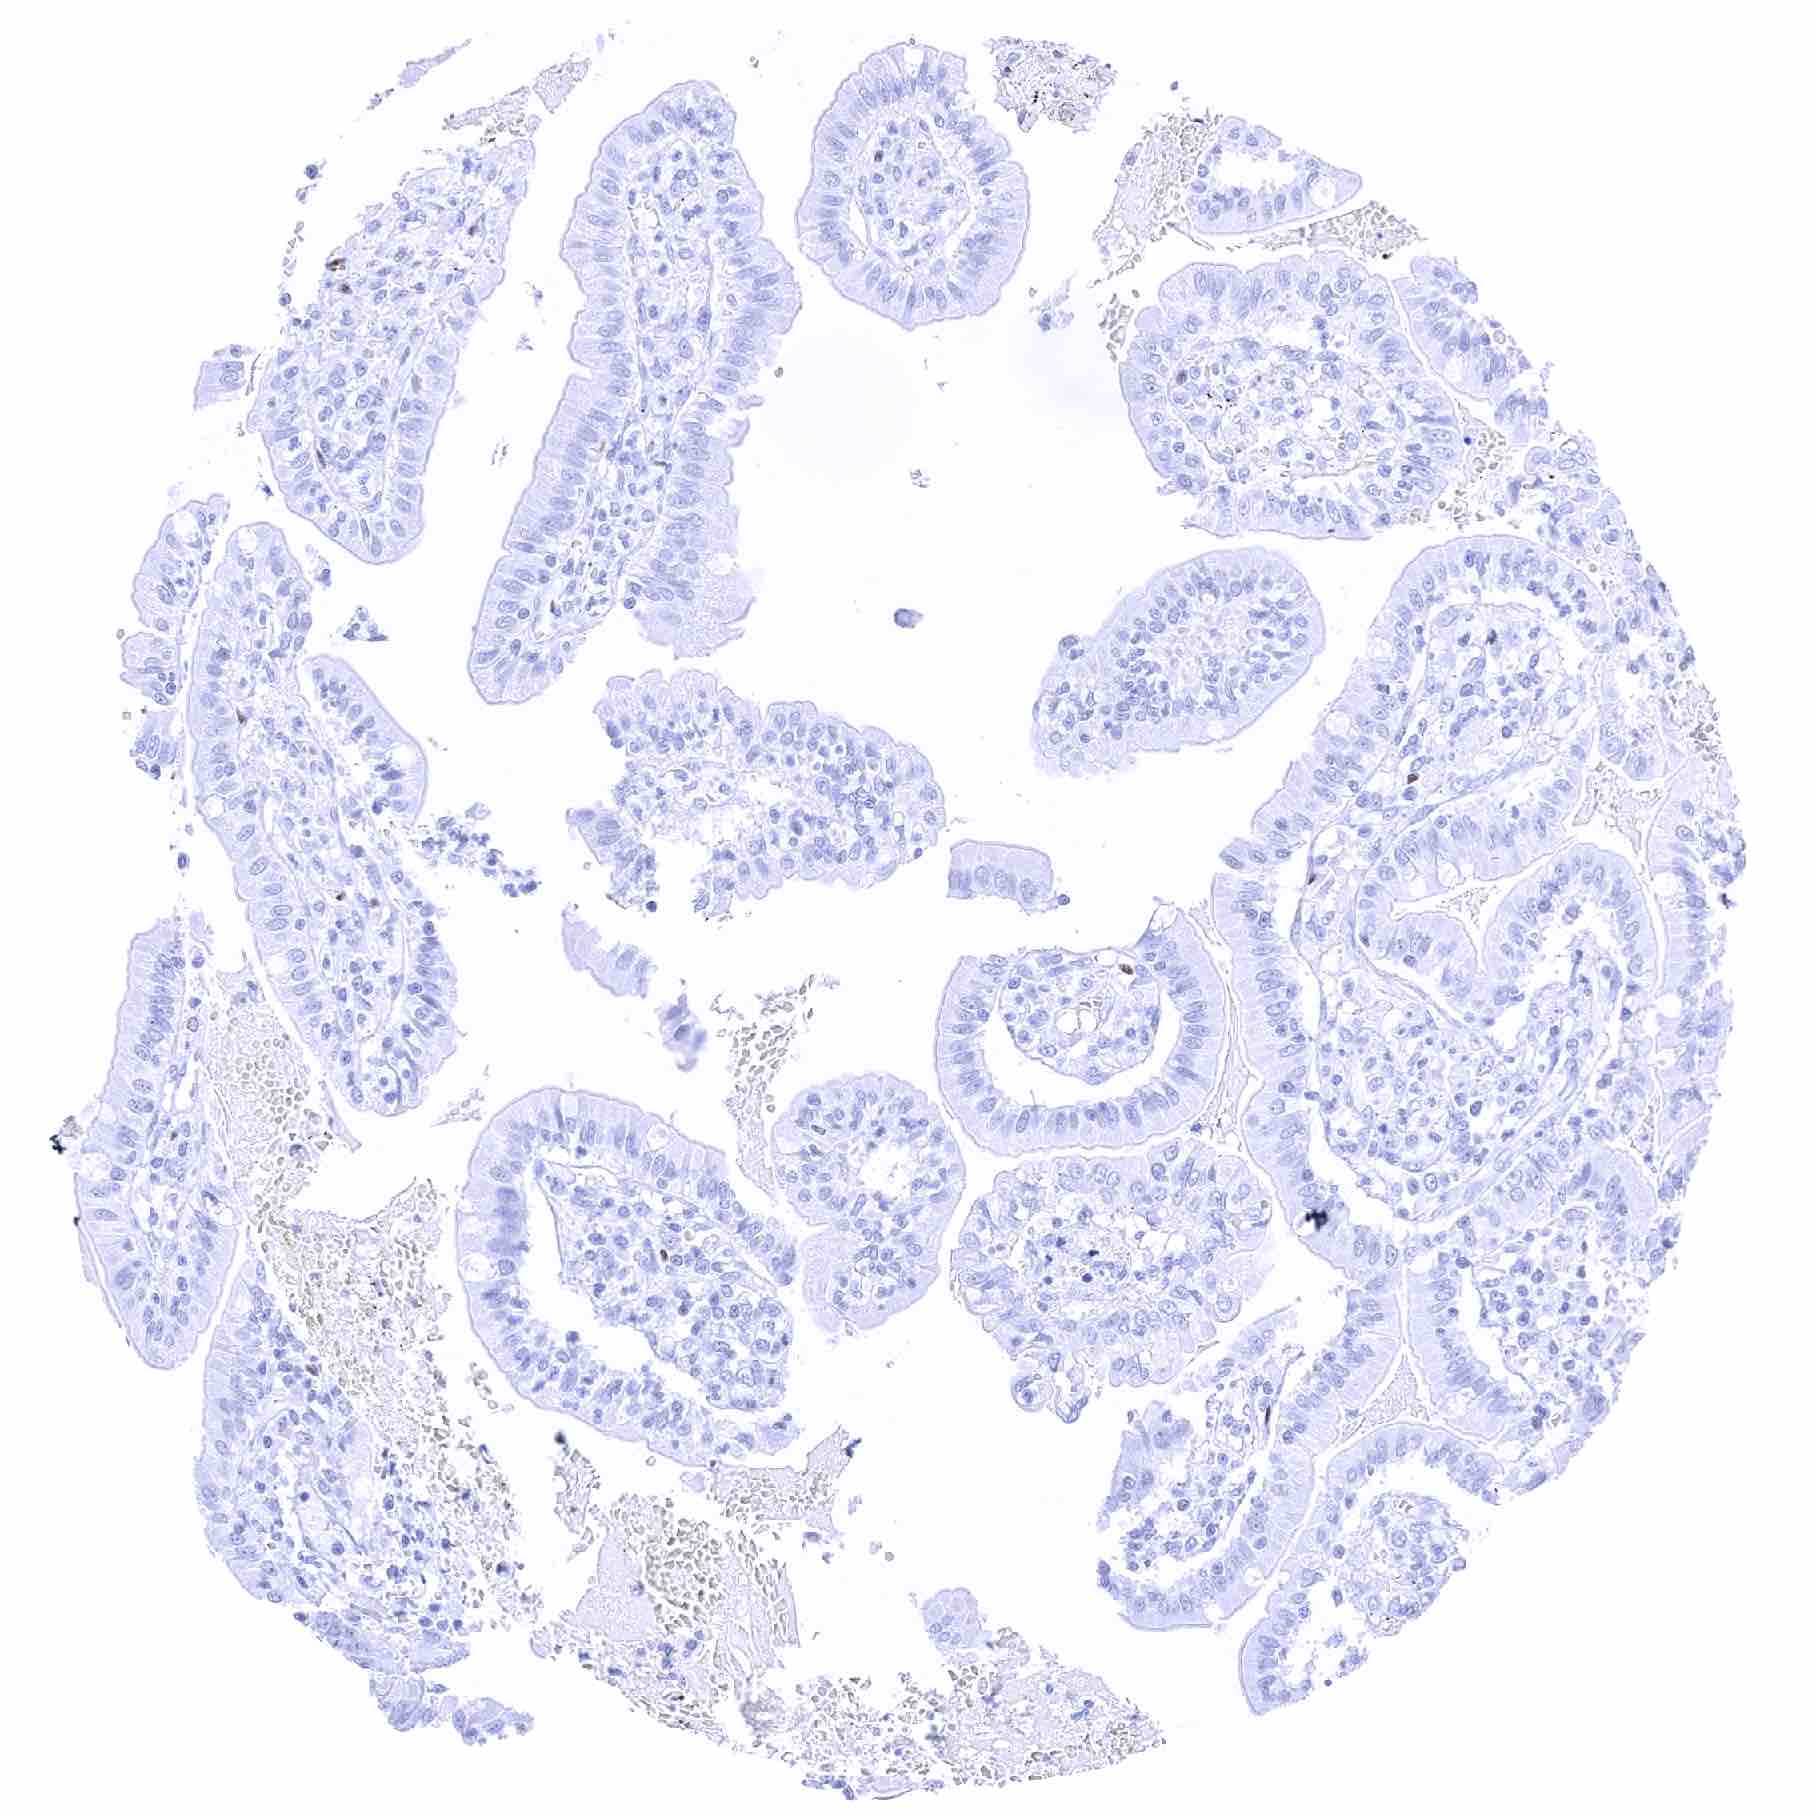

Prostate – Strong SOX2 positivity of a fraction of basal cells